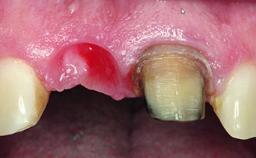

A 49-year-old female patient was referred for implant therapy to replace the upper right central incisor (tooth 11). The tooth had been assessed by an endodontist who diagnosed a vertical fracture of the root. The tooth had a hopeless prognosis and needed to be extracted. The patient was healthy and was not taking any medications. She was allergic to penicillin. The patient had high esthetic demands but her expectations were realistic. The extraoral examination revealed no facial asymmetries. The right temporomandibular joint demonstrated an opening click but was otherwise asymptomatic. The lip line was high with a significant gingival display.

Placement Protocol Early or late implant placement

Bone Volume Deficient vertically or deficient vertically AND horizontally